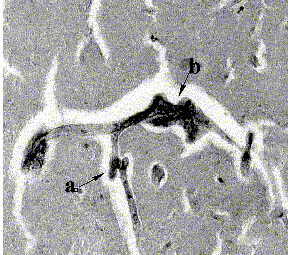

The general characteristics of both groups did not show statistical differences (p>0.05) (Table I). Tortuous arterioles were present in both control and status lacunaris groups. Six structural patterns (morphological profiles) of the tortuous vascular segments were observed: simple kink, loop, knot, tangle, coil, and wave (Fig. 1). Additionally, combinations of the above structural patterns were observed. In some blood vessels, multisegmented tortuosity was found (Fig. 2).

Fig2. multiple tortuous profiles in arterioles of the basal ganglia: (a) coil; (b) tangle, and (c) complex tortuosities. Diameter of the blood vessels are between 10-90 µm.